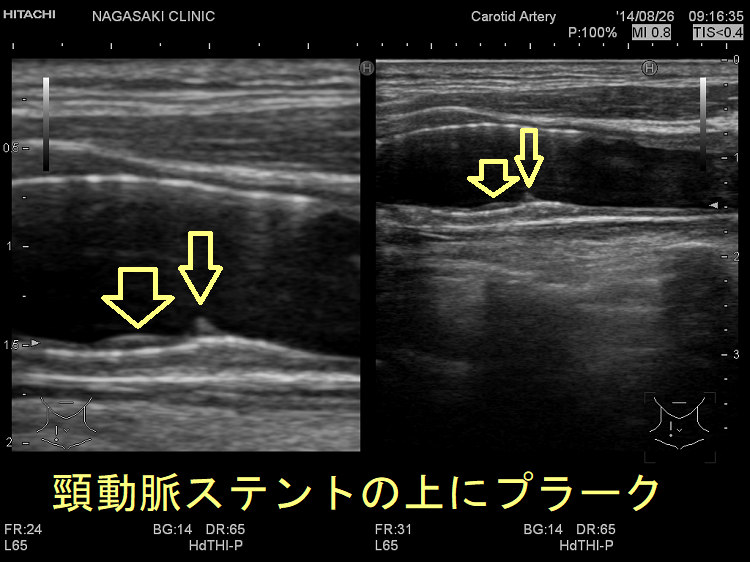

甲状腺機能低下症/潜在性甲状腺機能低下症/橋本病、糖尿病などでは動脈硬化が進み、頚動脈プラークにできた血栓が脳へ流れて脳梗塞。最悪、頚動脈自体の閉塞も。血管エコーでプラークを探す。動脈硬化血管は硬くもろく、大動脈では血圧に負けて大動脈瘤に。頸動脈閉塞度70%以上でカテーテル手術、ステント留置。時間が経つとステント上に新たなプラーク形成。内頸動脈ステント留置時、ガイドワイヤーで外頸動脈枝の上甲状腺動脈穿孔おこした報告あり。コレステロール/脂質塞栓が、網膜動脈を完全/不完全閉塞すると黄色斑(ホレンホースト斑)が生じる。

動脈硬化が進んだ血管にはプラーク(コレステロールエステルを大量に含んだ脂質の塊)(矢印)ができて、血管内が狭くなります。血管エコーでプラークを探す。動脈硬化した血管は硬くもろいため、大動脈では血圧に負けて大動脈瘤になることがあります(急性大動脈解離・大動脈瘤)。

(↓)デジタルハイビジョン超音波装置で見たプラーク。